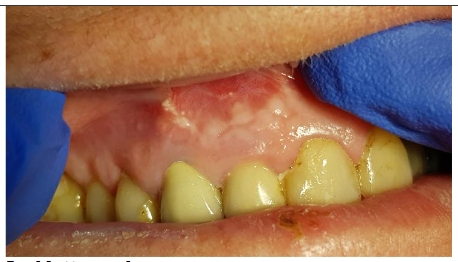

First clinical symptom was a vestibular abscess

A 65-year-old female patient with multiple medical conditions, including diabetes, a history of heart infarction (treated with PCI), hypertension, atrial fibrillation, and chronic anticoagulant therapy (dihydroxycoumarin and antiplatelet drugs), presented with a root cyst. The lesion appeared four years after successful endodontic and prosthetic treatment. The first clinical symptom was an abscess.